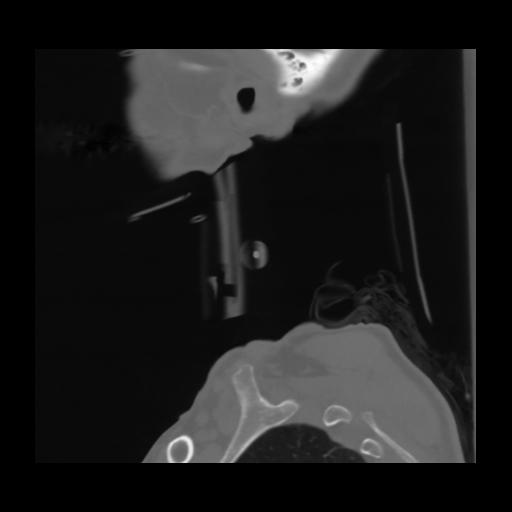

14 P.BLANDAS,,Sagittal,2.000,P.BLANDAS,Sagittal,